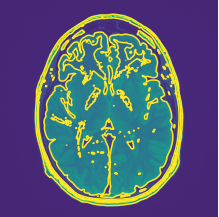

Contour calibration: Regarding MRI images, it is desired to have a higher contrast in the area of interest and lower on the rest. The images that are analyzed till now are in gray scale, hence the different variations in textures are not visible. To know the depth or height of a 3D plane contour lines can be used. It is a function of two variables in a curve along which the function has a constant value so that the curve joins points of equal value. A gray-scale image can also be seen as a 3D representation of the values ranging from 0 to 255 for each pixel of which contour can be plottedkim2014relationship . In this experiment, the MRI has a size of 150 ×\times150 and the contour line can be used to define various colors to the images with varying gray scale. An example showing the contour plot for an MRI sample is shown in Fig. 6(a).

Refer to caption

(a) Contour plot for gray scale MRI image.

(b) Sobel edge detection for gray scale MRI image.

(c) Difference contour for gray scale MRI image

Figure 6: An example of special preprocessing technique.

Differencing: In this phase, the matrices of grayscale MRI image is subtracted from the Sobel edge MRI image are on a pixel by pixel basis. If different contour intensity is present in original contour and Sobel edge contour then take the higher value of intensity. This phase reduced the less oriented regions and gave proper intensity uplifting in the regions of interest. An example showing the contour matching operation over the difference image for an MRI sample is shown in Fig. 6(c).